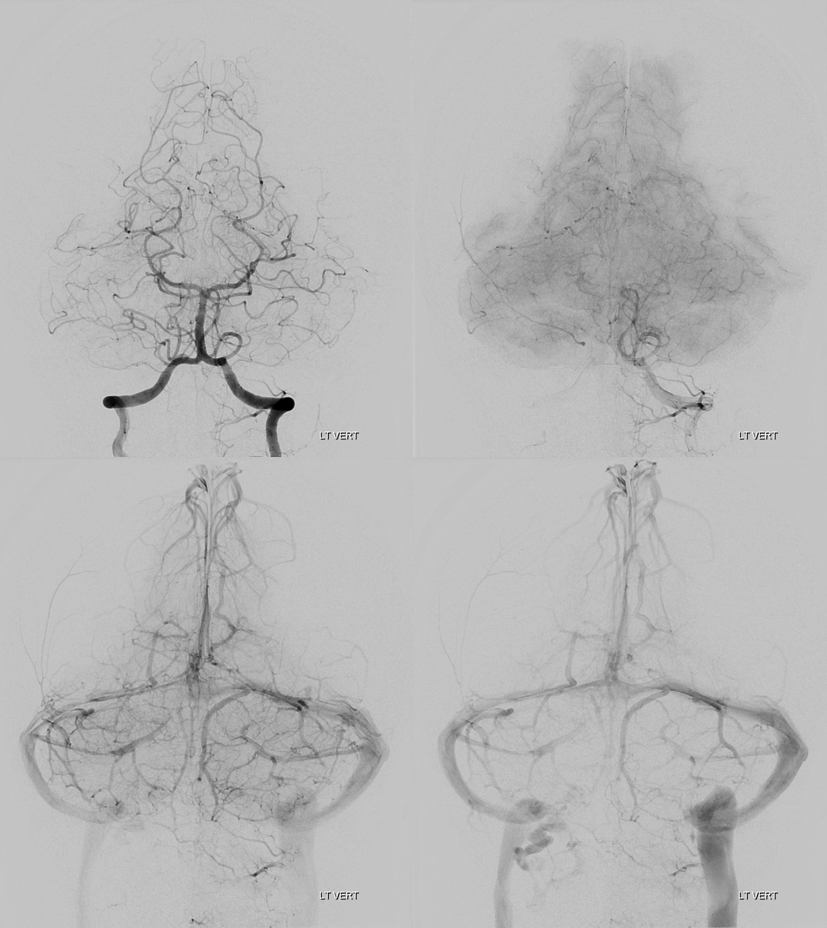

Vert